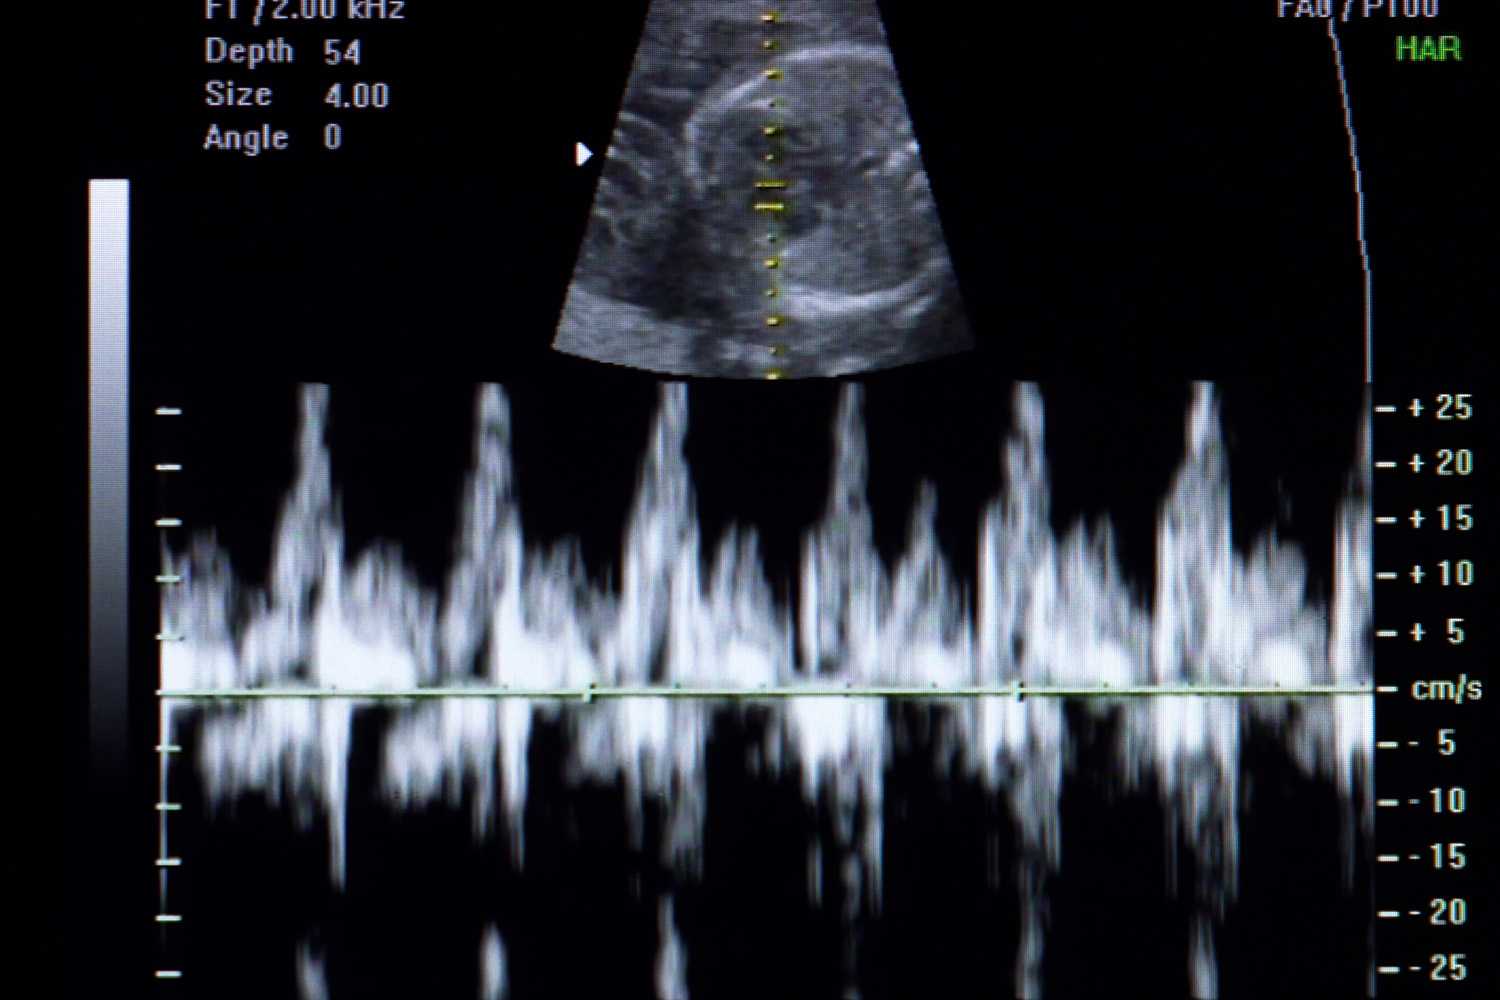

Fully accredited by the ACGME, our fellowship provides a comprehensive clinical and academic foundation, preparing the next generation of leaders in Maternal-Fetal Medicine. Each fellow’s career path is unique, and our mission is to cultivate individual strengths and interests while ensuring exposure to the full breadth of our subspecialty. Our fellows receive rigorous training in all aspects of MFM, including fetal medicine and surgery, ultrasound and prenatal diagnosis, labor and delivery, antepartum inpatient care, critical care, and women’s global health. In addition, opportunities abound in laboratory and translational research, clinical research, public and community health, as well as patient safety and quality improvement. This individualized and flexible approach allows each fellow to develop deep expertise in areas aligned with their career aspirations, while benefiting from the diverse resources and mentorship available at a leading academic medical center.

Our fellowship is based at Jack D. Weiler Hospital, a 421-bed private hospital and New York State–designated Regional Perinatal Center. Training is supported by four ultrasound units that serve as a major referral network for complex fetal anomalies. Fellows learn in a highly collaborative environment, leading weekly multidisciplinary conferences with neonatology, anesthesiology, and other maternal and pediatric subspecialties.